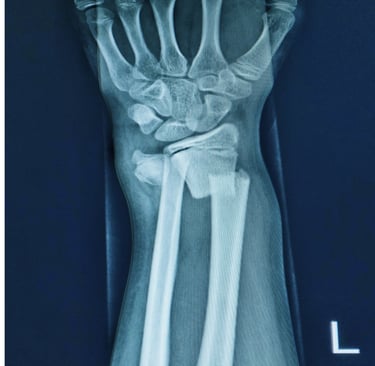

Colles fractures are among the most common wrist injuries, especially in high-impact situations like motorbike accidents and cycling accidents. The injury typically occurs when a person instinctively throws out their hand to break a fall. The force drives the wrist backwards, causing a break in the radius bone near the wrist joint.

Immediately after the injury, most people feel a sharp, intense pain in the wrist, often accompanied by swelling, bruising, and an obvious deformity. The wrist may look bent or twisted unnaturally. Movement becomes very limited, and any pressure on the area can be excruciating.

Colles fractures often require realignment of the bone (reduction), and in many cases, immobilisation in a cast or even surgery. Leaving the fracture untreated or delaying care can lead to long-term problems like misalignment, reduced mobility, or nerve damage. Early treatment gives the best chance for a full recovery.

Treatment depends on the severity of the fracture. Milder cases may be treated with a plaster cast for 6–8 weeks. More complex breaks may require surgical fixation with metal pins, plates, or screws.

A typical example might involve a Colles fracture to the left wrist only, sustained in a motorbike collision. The individual makes a good recovery after more than 12 months, with only occasional minor pain or stiffness.